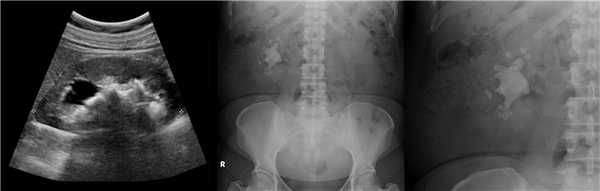

В марте 2002 г. в связи с эпизодом лейкоцитурии лечился у нефролога; при контрольном УЗИ впервые диагностированы изменения в мочевом пузыре и паравезикально слева. При повторном УЗИ выявлено (рис. 1а): правая почка увеличена в размерах (длина 12,7см; толщина паренхимы 1,6 см); чашечно-лоханочная система не расширена. Левая почка отсутствует. Стенки мочевого пузыря не изменены; в просвете слева определяется округлое образование 3,5 x 4,6 x 5,0 см с неоднородным содержимым (объем около 40 мл). Заключение: аплазия левой почки; уретероцеле слева.

а) Эхограмма.

б) Компьютерная томограмма.

в) Схема КТ.

При экскреторной урографии - правая почка компенсаторно увеличена (длина 13 см), без нарушения уродинамики. Слева почка не контрастируется. Заключение: аплазия левой почки.

Компьютерная томография (КТ): в проекции устья левого мочеточника и на фоне мочевого пузыря слева определяется дополнительная тень 3,1 x 4,0 x 4,0 см с четкими контурами и плотной стенкой. Мочеточник выше устья расширен до 1 см. Заключение: КТ-картина уретероцеле слева, уретерэктазия слева (рис. 1 б, в).